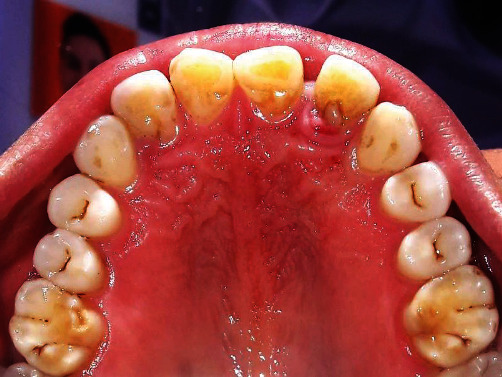

腭根状沟(PRG)是牙根发育异常的一种表现,一旦出现就会引起牙周和牙髓问题。目前有多种不同的治疗方法,如牙周翻瓣手术、牙髓治疗、用各种粘结剂封闭 PRG、骨内缺损植骨术、封闭或去除 PRG 后拔牙并有意识地重新种植、牙髓治疗以及使用各种生长因子。治疗的成功与否取决于 PRG 的类型、深度和范围、是否存在牙槽骨内缺损、相关牙齿的活力以及用于封闭 PRG 的材料类型。本研究报告了一名 44 岁全身健康的女性患者使用 Biodentine® 和富血小板纤维蛋白治疗 PRG 的情况。

Palatal radicular groove (PRG) is developmental anomaly of root, which when present is associated with periodontal and endodontic problems. Different treatment modalities are available for its management, such as periodontal flap surgery, endodontic management, sealing of PRG with various cements, bone graft procedure for intrabony defect, extraction with intentional replantation after sealing or removal of a PRG, and endodontic treatment as well as the use of various growth factors. Success of the therapy depends on the type, depth, and extent of PRG, presence or absence of intrabony defect, vitality of involved tooth, and types of materials used to seal PRG. This study reports management of PRG with Biodentine® and platelet-rich fibrin in a 44-year-old systemically healthy female patient.